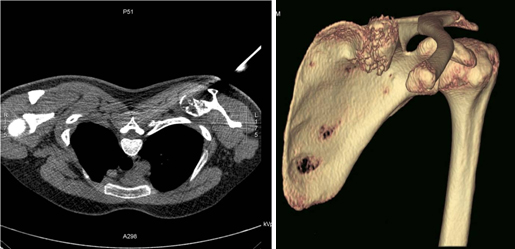

척추, 골반골의 종양이나 장관골의 피질에 위치한 종양을 판단할 때, 그리고 종양의 폐 전이 유무를 판단하거나 복부 장기로의 전이 등 종양의 진행단계를 결정할 때에 유용하게 이용되고 있으며, 원발암의 추적 조사 등에도 이용되고 있습니다. 침생검 시행시 원발 부위를 정확히 겨냥하기 위한 영상 도구로도 흔히 사용되며 골반골이나 견갑골 등 3차원적으로 복잡한 구조를 가지는 골격부위에서 발생한 악성 골종양의 수술 전 평가로써 3차원적으로 재구성한 전산화단층촬영(CT)을 사용하기도 합니다. 그 밖에 3차원 혈관조영 전산화단층촬영(CT)은 수술 전 종양의 혈관 분포도와 종양의 입체를 정확히 확인하는데 도움이 됩니다.

[ 좌측 견갑골에 발생한 연골육종에 대한 전산화단층촬영(CT)유도하 생검 모습과 3차원 재구성 CT ]